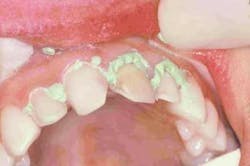

Preparation of the four incisors was then initiated using diamond burs from the Shofu Contemporary Cutting Kit (Figure 5). With the high-speed ElectroTorque KaVo handpiece, a small round diamond (0872-1) was used to outline the peripheral margins of the preparations (Figure 6). By scoring the facial surface of the incisors with the depth cutter (0897-1) (Figure 7), smooth and uniform tooth structure removal using a coarse tapered diamond (0835C-1) was facilitated (Figure 8). As tooth nos. 9 and 10 were prepared, it came time to address the gingival contour issues of the inflamed interproximal gingiva.